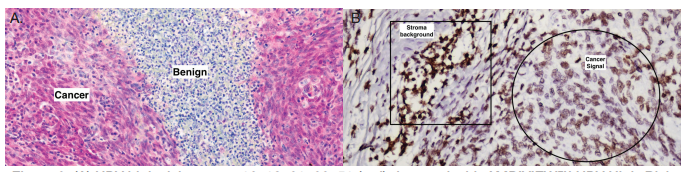

AMPIVIEW™ RNA探针与竞争对手的产品相比,具有更高的特异性和更低的背景(图3)。

图3.(A)用AMPIVIEW™ HPV高危RNA探针在宫颈癌组织中检测到HPV高危型16、18、31、33、51(红色)。(B)竞争对手的高危HPV探针(棕色)在相同条件下进行测试。